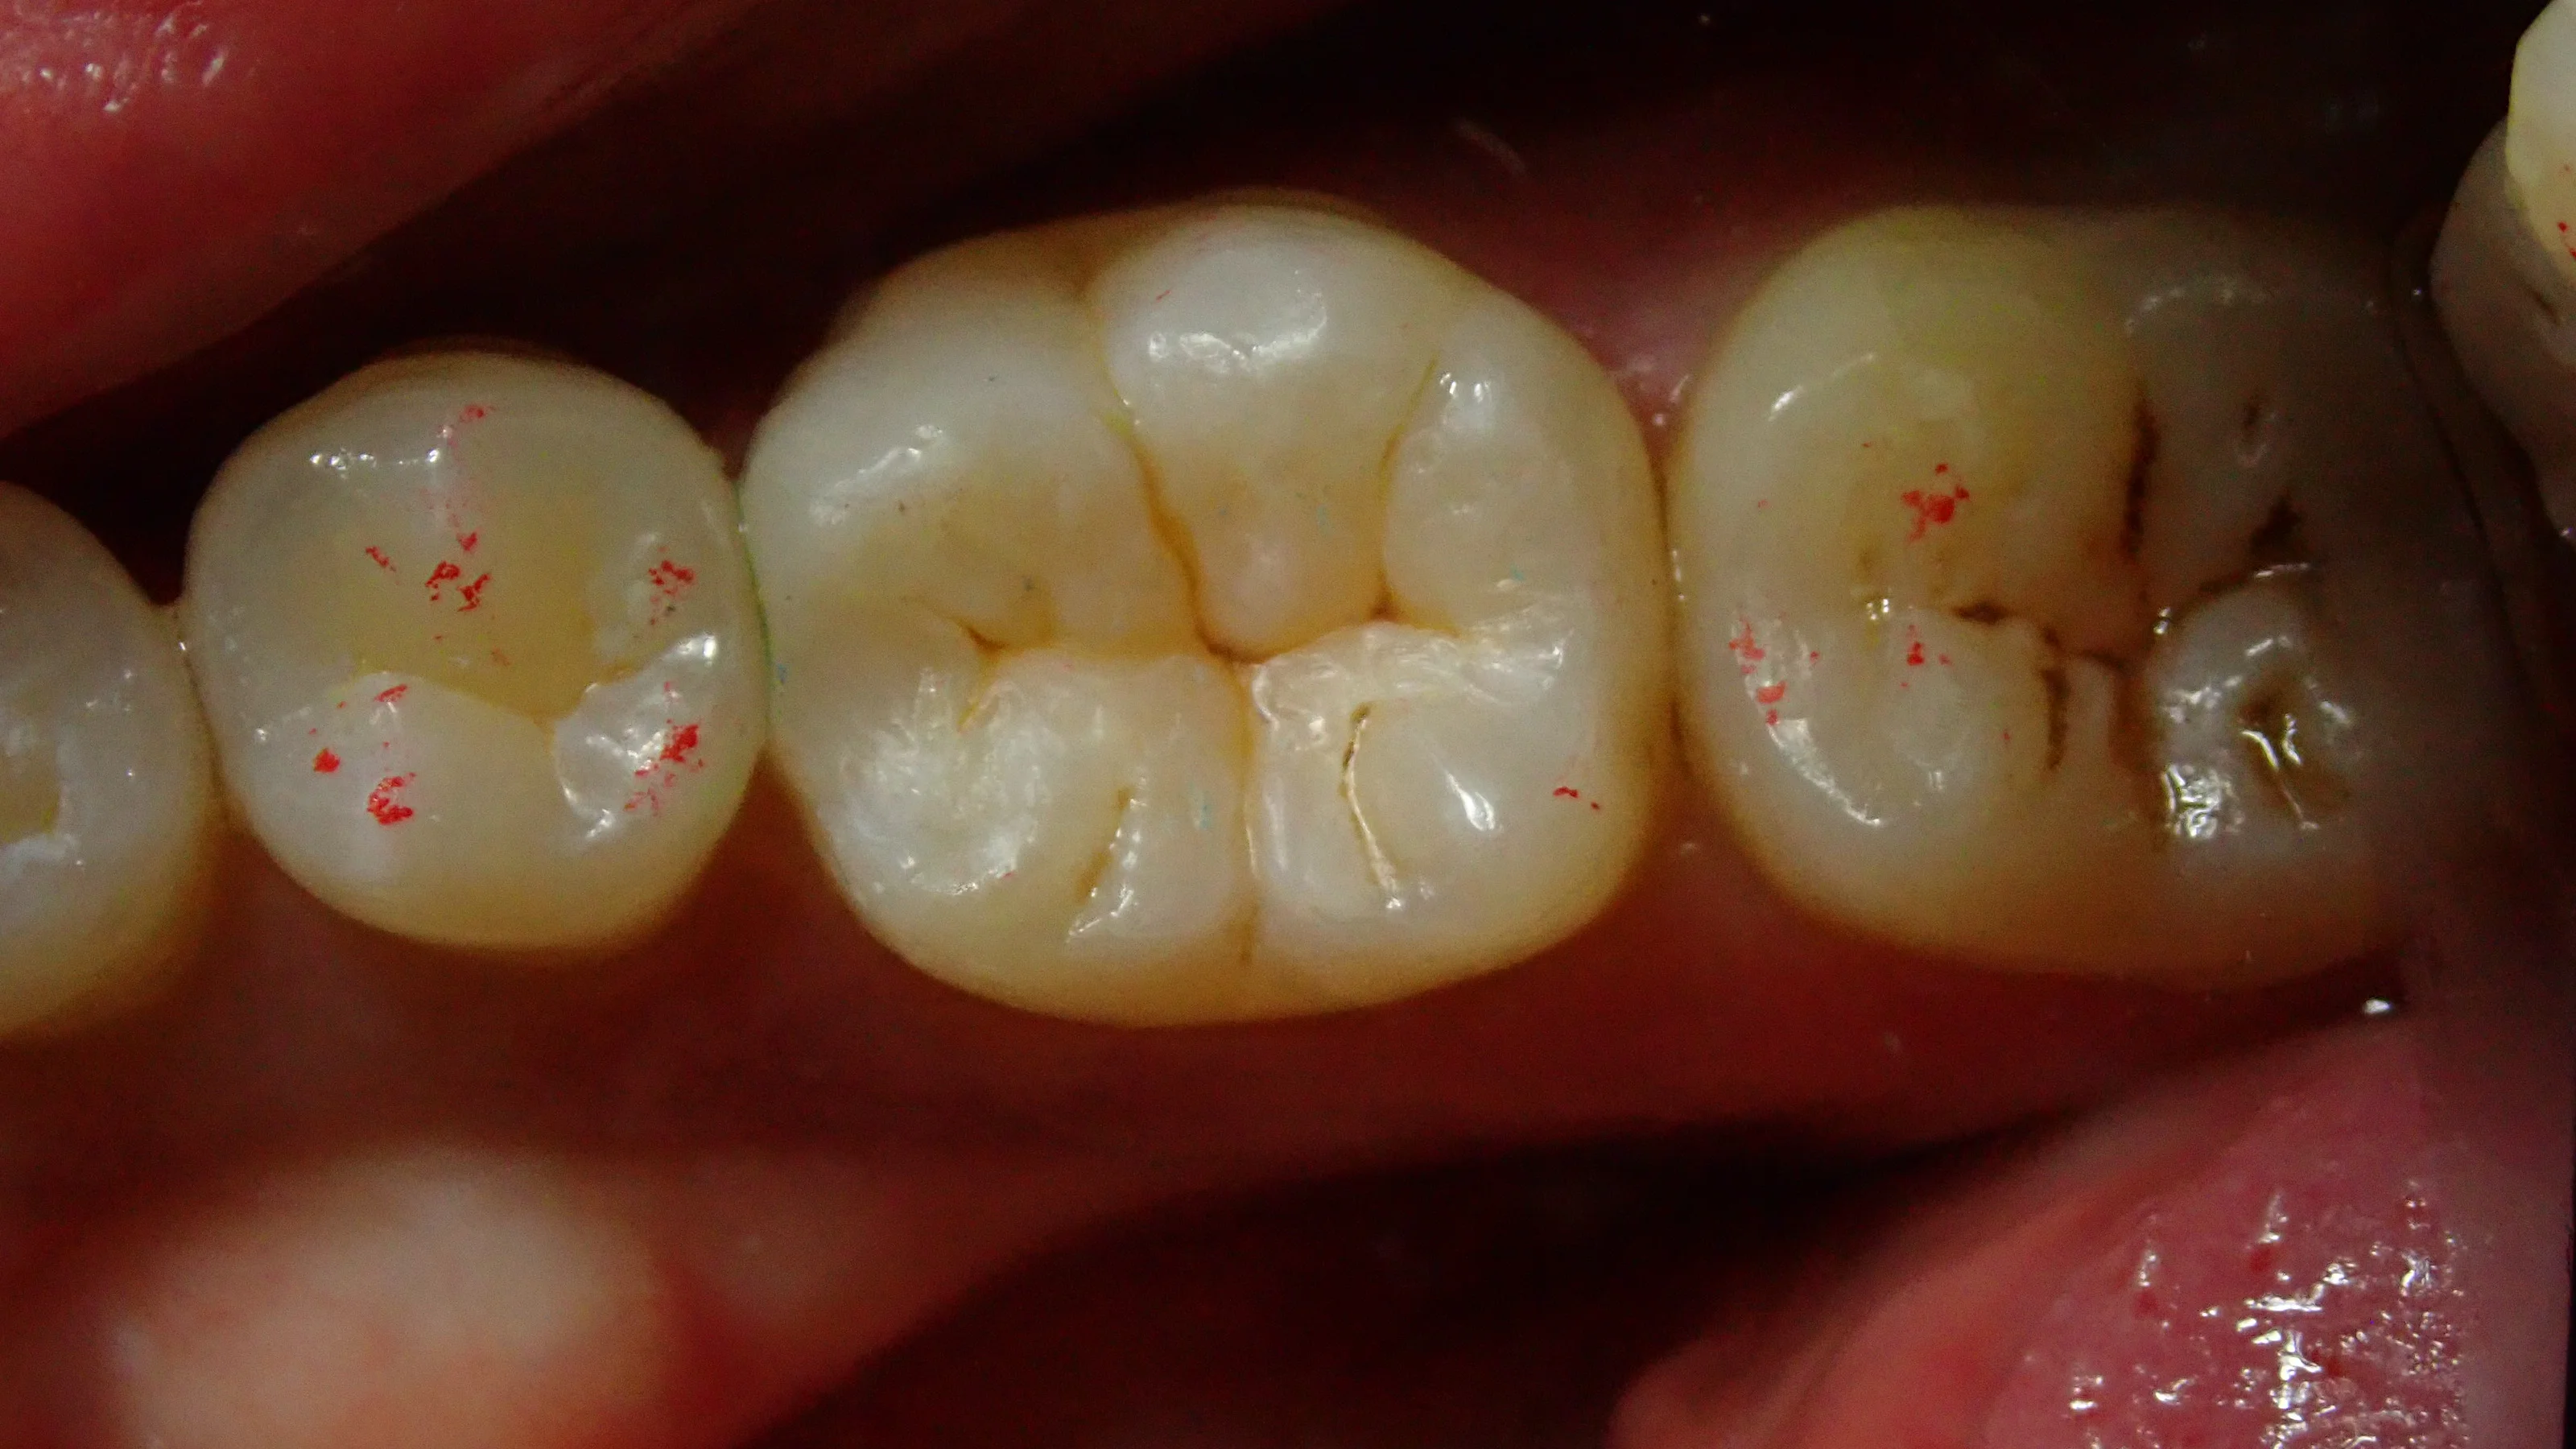

充填後に咬合調整を終えた写真です。

比較的良い感じにステイニング(溝の部分の着色等)も出来たと思います。

そして最後に、術前術後の比較写真がこちらです。

仕上がりにご満足いただけたようで、次回4月に右上の奥歯を行う事となりました。

歯の間の部分もフロスを通しても引っ掛かりが全くない様に仕上げましたので、しっかりとフロスを通していただいて大丈夫です!